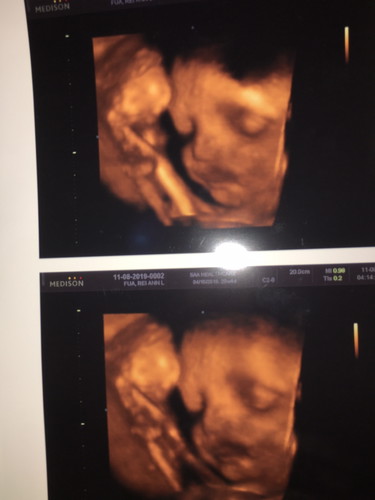

3D CAS

eto na nga. nakta ko agad bibig ni baby girl, nagtanong agad ako kay ob kung may problema ba ung bibig nya. sagot nman sken ni ob normal lang nman daw lahat. lip nose intact. wag daw ako mabahala kase cas nman yung gnawa samen malalaman kung my mga problema si baby pero awa ng dyos okay po sya. ? nakukuha lang daw ang bingot sa lahi lahi kaya wag daw po maniwala na kapag nadulas ka e mabbngot na agad si baby. napanatag na utak ko kakaisip ????

May ganyan din po kaming nakita nung pina 4d ultrasound namen si baby. Pero inexplain naman ni doc na parang shadow lng ng placenta.

Wow mummy congrats po, tangos ng ilong ni baby girl hehehe ilang months na po ba kayo ngyon para ma cas?

nagpacas po ako mag 8mons na po sya.

7months po coming 8 na rin po.

mag8mons na po. 3800 po